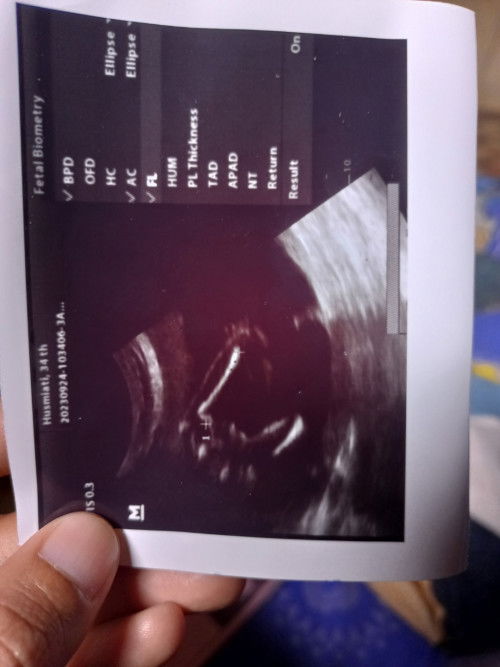

Grup HPL: Januari 2024

Jenis kelamin UK 21 Minggu 6 hari

Mau tanya bunda bunda saya tadi USG UK 21 Minggu 6 hari, Alhamdulillah semuanya normal,kata dokter tadi jenis kelaminnya cewek,mau tanya klo gambar seperti itu apa benar jenis kelaminnya cewek menurut pengalaman bunda,terima kasih

Đã trả lời 3y trước bởi Ria Novita

yang bisa baca gambar USG hanya dokter bund.. kita hanya bisa baca yang tulisan di sampingnya itu